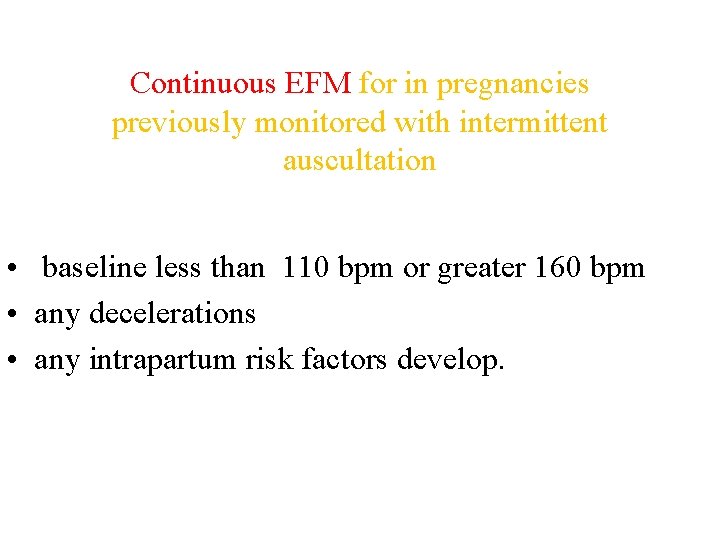

Continuous EFM for in pregnancies previously monitored with intermittent auscultation • baseline less than 110 bpm or greater 160 bpm • any decelerations • any intrapartum risk factors develop.